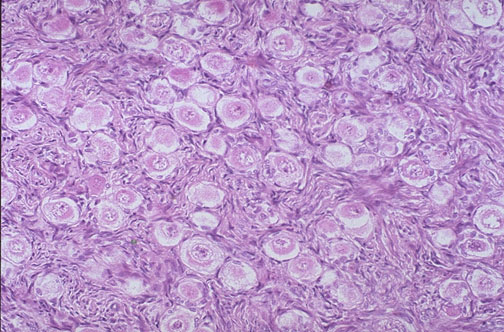

| Normal fetal ovary at high magnification reveals numerous primordial follicles and little intervening stroma. The number of follicles will begin to decrease even before birth, and by puberty there will only be several hundred that remain to undergo ovulation during reproductive years. |